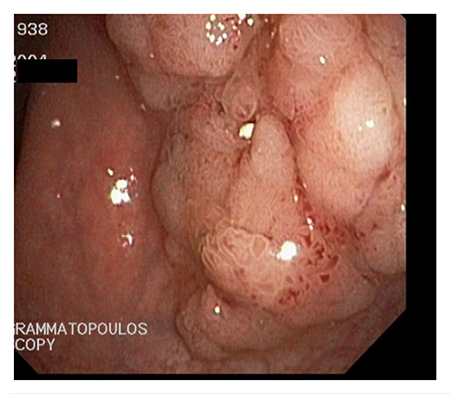

Endoscopic Removal Of Large Sessile Polyps And Submucosal Lesions

A sessile polyp is any flat wall growth without a stalk, usually detected during an endoscopic exam.

Sessile polyps differ in size, ranging from a few milliliters to several centimeters, and may be located anywhere along the digestive tract.

Submucosal lesions are tumors – usually benign, but also malignant in some cases – that are located inside the digestive tract wall. In the majority of cases they are covered by normal mucosa. When the endoscopy specialist detects a sessile polyp or a submucosal lesion, the first thing they consider is how to remove it completely, without causing any complications or prompting any future relapse. The most difficult to manage polyps are the ones located in the second part of the stomach duodenum, as well as the adenomas of the ampulla of Vater.

Our Hospital meets all these conditions. As a result, the endoscopic procedures are completely safe. Sessile polyps that are over 1 cm in size require special endoscopic management during polypectomy. A necessary condition is the submucosal injection of normal saline solution, with or without epinephrine, along with blue de methylene or indigo carmine. The infusion helps separate the mucosa and submucosa from the muscular layer. This technique also offers the endoscopy specialist the chance to understand whether they can remove the lesion. When the base of the polyp rises smoothly and easily, then it is possible to remove the polyp. The infusion may reduce the risk of bleeding and perforation following polypectomy.

Polyps that are over 2 cm in size may be removed in fragments or using the endoscopic submucosal dissection (ESD) method. Submucosal lesions are removed using a different procedure. Initially, the mucosa is lanced using a special lancet and the lesion is exposed. It is then separated from the surrounding tissue and removed.